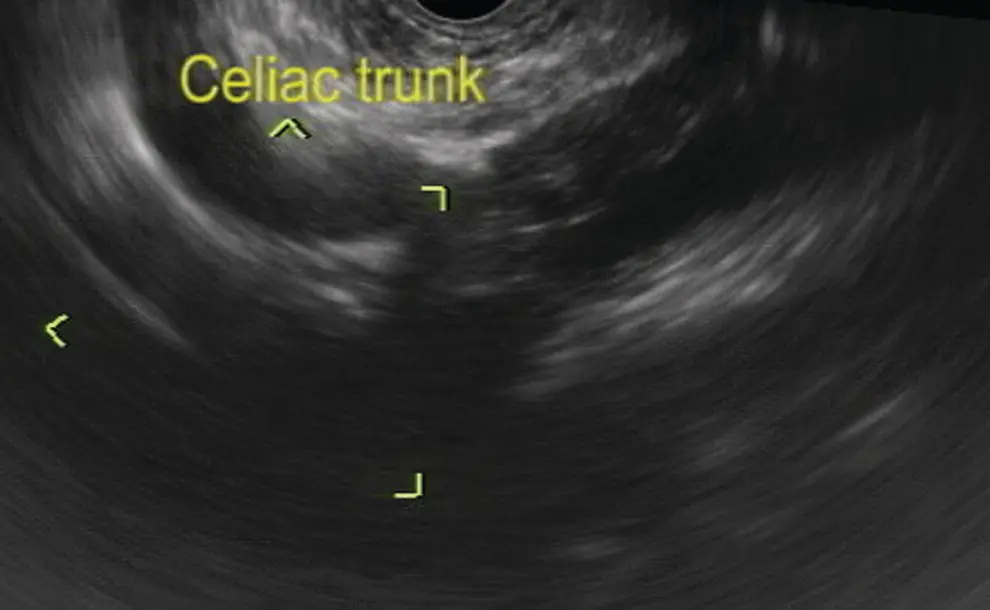

With the probe at the level of the diaphragmatic hiatus, the longitudinal aorta and celiac artery origin are the most recognizable reference points ( Figure 7.2), demonstrated as tubular longitudinal structures. Here, rotation of the probe counterclockwise will bring into view the liver parenchyma and its vascular structures ( Figure 7.3).

Figure 7.2 Celiac artery imaging by linear ultrasound.